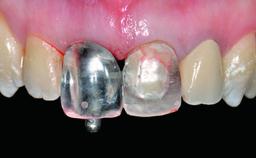

Replacement of a Failing Restored Upper Right Central Incisor, Ridge Preservation and Early Placement of an RC Bone Level Implant

A 23-year-old female, healthy and non-smoking patient had had tooth 11 temporarily restored following a trauma in adolescence. As the patient’s growth had since come to an end and the crown had fractured, she requested an implant-supported restoration of tooth 11. Moreover, the contralateral tooth 21 presented an old composite restoration at the mesial incisal edge. The periodontal tissues were healthy with periodontal probing depth values below 3 mm, but some inflammation was observed around the semi-submerged root of tooth 11.

Loading Protocol Conventional or early

Retention Cemented, with prosthesis margin < 3mm submucosal Cemented, with prosthesis margin < 3mm submucosal